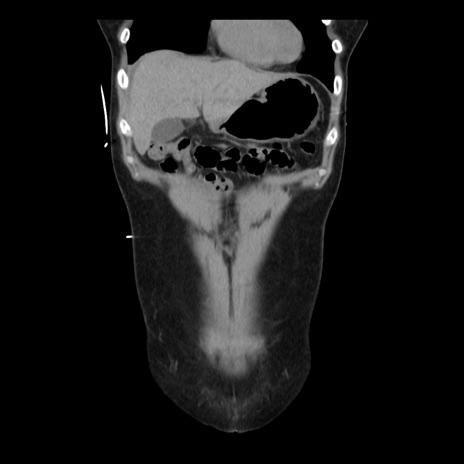

横断像

【症例】 50歳代女性

【主訴】 腹痛

【現病歴】前日生レバーを食べた。今朝に排便あり。 昼前に突然発症の腹痛を生じ、当院救急外来を受診した。

【既往歴】 子宮筋腫にてで子宮全摘後

【身体所見】 意識清明、腹部:平坦、軟、下腹部やや左を中心に圧痛・反跳痛あり、筋性防御あり

【データ】WBC 7800、CRP 0.07